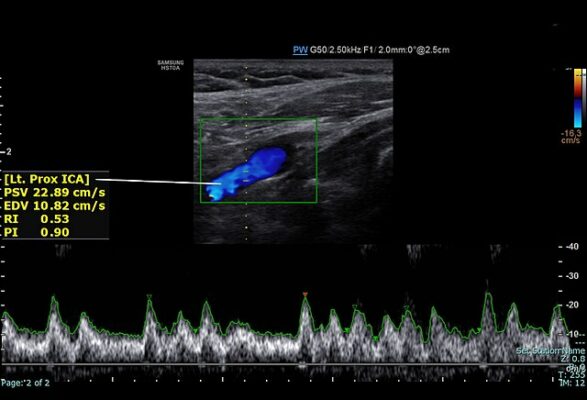

Karotis Doppler Ultrasonografisi:

Bu test, karotis arter hastalığının tanısında altın standarttır ve genellikle ilk başvurulan yöntemdir.

Ses dalgaları kullanarak şah damarlarının canlı, hareketli bir haritasını çıkarır. Boynunuza sürülen küçük bir miktar jel üzerine ultrason probu konularak yapılır.

Bu yöntemle damar duvarının yapısını, intimal kalınlaşma gibi en erken değişiklikleri, mevcut plakların yerini, boyutunu, yapısını (yumuşak mı, kireçli mi) ve en önemlisi damarda yüzde kaçlık bir darlığa yol açtığını net bir şekilde görebiliriz. Doppler özelliği sayesinde damar içindeki kan akımının hızını ve yönünü de ölçerek darlığın ciddiyeti hakkında kesin bilgi ediniriz.

Tamamen ağrısızdır, radyasyon içermez, hazırlık gerektirmez ve yaklaşık 20-30 dakika içinde sonuç verir.

- Sol proksimal internal karotid arter normal spektral doppler

Eğer Doppler ultrason sonuçları yetersiz kalırsa veya cerrahi ya da stentleme gibi bir tedavi planlanıyorsa, damarların anatomisini üç boyutlu olarak daha detaylı görmek için ek testlere ihtiyaç duyulabilir.